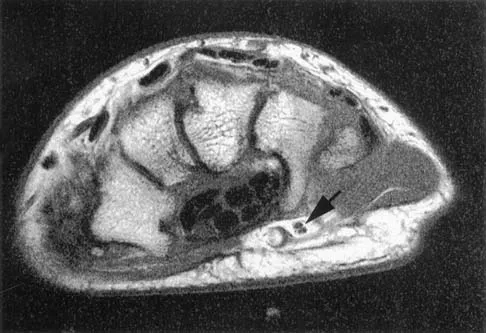

The arrow in the axial T1-weighted MRI scan shown in Figure 18 is pointing to which of the following structures?